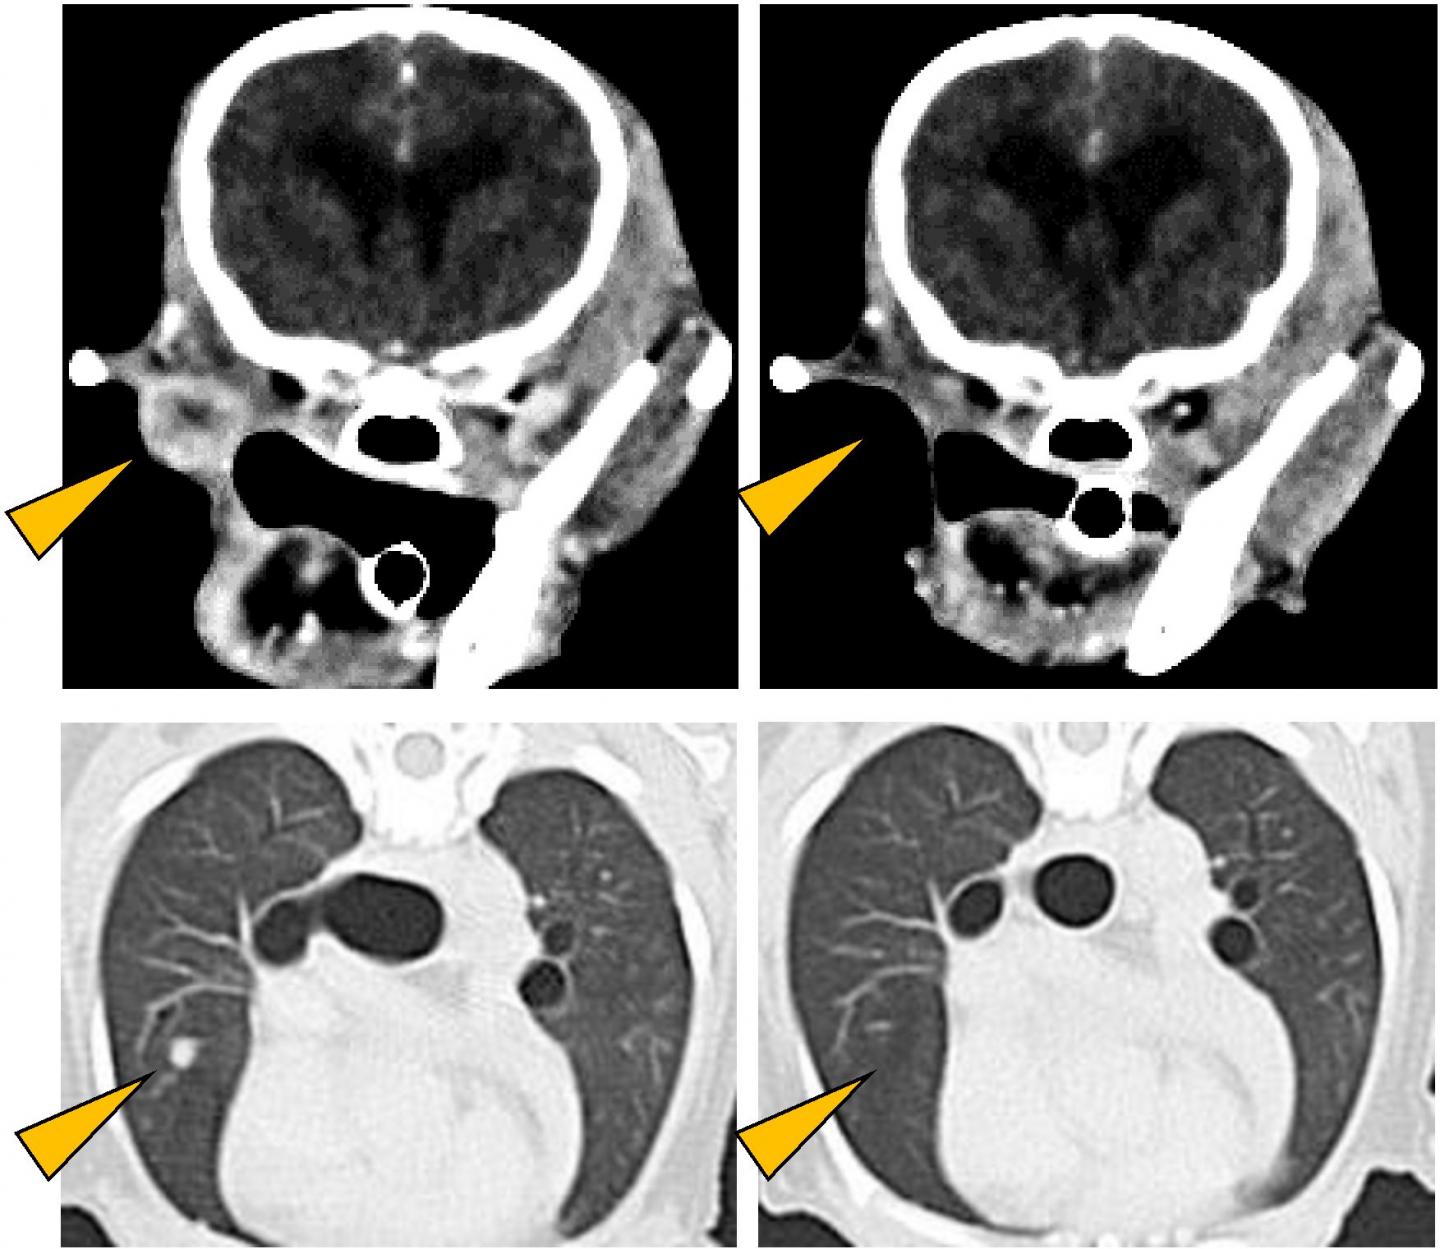

image: Antitumor effect of anti-PD-L1 antibody. CT images of oral malignant melanoma (upper left) and its lung metastases (lower left) observed in a Pomeranian (12 years old, male). As a result of treatment with anti-PD-L1 antibody, all detectable tumors disappeared (right panels; Naoya Maekawa, et al. npj Precision Oncology. February 12, 2021).

The survival time of dogs treated with the chimeric antibody was significantly longer, with a median survival time of 143 days, compared to 54 days for the control group, from historical data. Thirteen dogs had measurable cancer (i.e., at least one tumor >10 mm in diameter in CT scan), while 16 had non-measurable cancer (all tumors